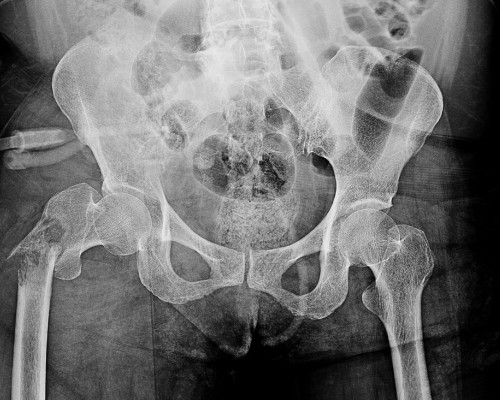

If needed, we'll arrange X-rays or an MRI right away to understand what's going on inside your hip joint. Dr. Mehta will personally review the results with you.